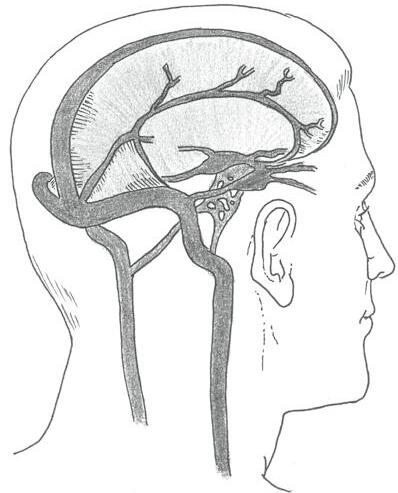

Zásobení mozku okysličenou krví zajišťují čtyři hlavní arteriální zdroje – dvě vnitřní krkavice a dvě páteřní tepny:

• pravá a levá vnitřní krkavice (arteria carotis interna dextra et sinistra) vznikající po rozdělení pravé a levé společné krkavice na zevní a vnitřní větev;

• pravá a levá vertebrální tepna (arteria vertebralis dextra et sinistra).

Levá společná krkavice (arteria carotis communis sinistra) odstupuje přímo z oblouku srdečnice neboli aorty. Pravá společná krkavice (arteria carotis communis dextra) je větví hlavopažního kmene (truncus brachiocephalicus), který se po krátkém průběhu dělí na zmíněnou pravou společnou krkavici a pravou podklíčkovou tepnu (arteria subclavia dextra).

Páteřní tepny jsou větvemi podklíčkových tepen. Pravá páteřní tepna odstupuje logicky z pravé podklíčkové tepny (arteria subclavia dextra) a levá páteřní tepna vychází z levé podklíčkové tepny (arteria subclavia sinistra). Okysličenou krví zásobují mozek, míchu, meningy a hluboké svaly krku.

Obě páteřní tepny se po vstupu do mozkovny spojují v bazilární tepnu (arteria basilaris). Tato tepna je propojena s oběma vnitřními krkavicemi arteriálními spojkami a na spodní straně mozku vytváří Willisův arteriální okruh (circulus arteriosus Willisi), ze kterého odstupují jednotlivé tepny zásobující přední, střední a zadní část mozku.

Odkysličenou krev z mozku odvádějí mozkové žíly (venae cerebri, jednotné číslo vena cerebri) ústící do systému žilních splavů (sinus durae matris). Jejich stěnu tvoří tvrdá plena mozková. Odvádí krev do krčních žil – zejména do vnitřní jugulární žíly (vena jugularis interna).